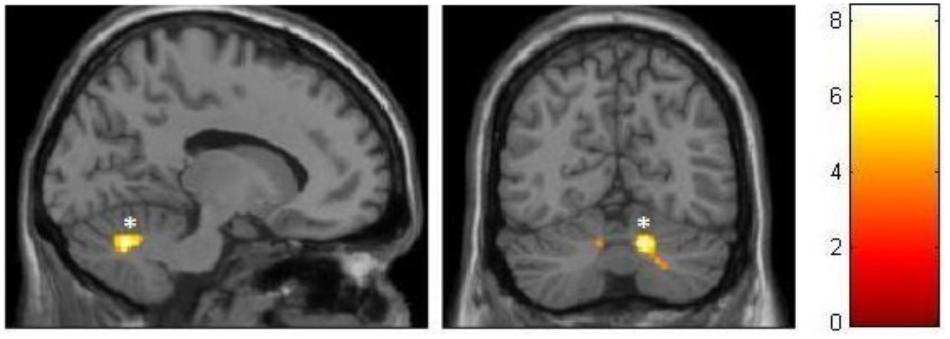

For the ballet group, the VBM analysis revealed significantly larger cluster-based FWE-corrected gray matter volumes within the inferior and posterior areas of the right cerebellar hemisphere, right parahippocampus, right cingulate motor cortex, and right insula (Figure 3). Additional tendencies at uncorrected level (p < 0.001) could be observed in the vermis, right posterior hippocampus, and right posterior thalamus. The respective MNI coordinates as well as the cluster sizes are listed in the Table 4.

FIGURE 3. VBM observed GM increments in the ballet group compared to the control group. ∗FWE-corrected at the cluster level.